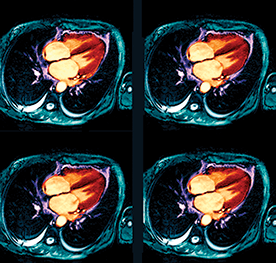

Utilizing ventricular assist devices for adult congenital heart disease patients who progress to end-stage heart failure using advanced cardiac MRI and CT with 3-D printing technology to help plan surgery and optimize outcomes

Utilizing 4-D £ow MRI with computational £uid dynamics to spare the native valve in patients with ascending aortic aneurysms